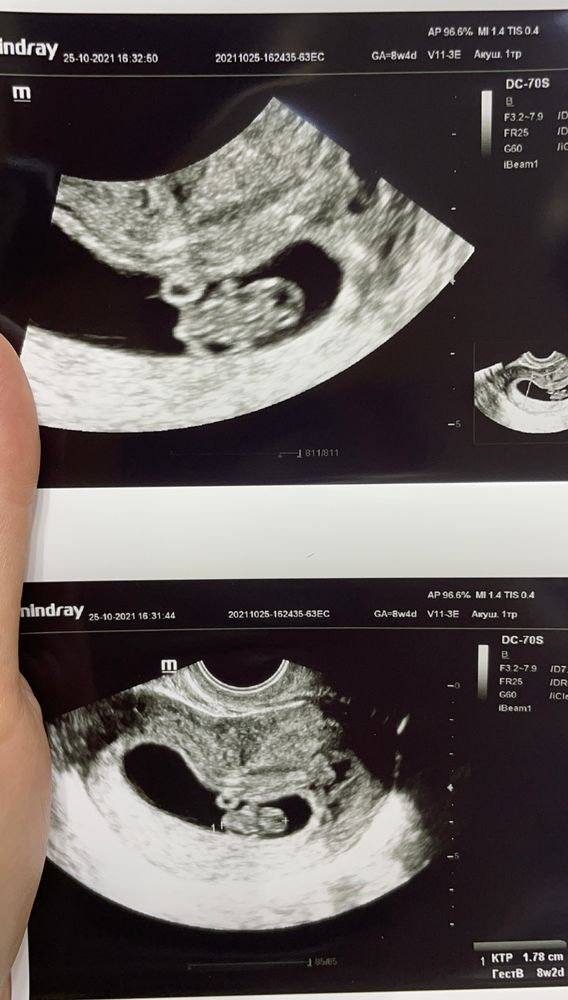

Наталья , вот узи с дочкой 8+4 недели, тот же самый «кружочек», здоровый пупс уснул только что)

не переживайте)